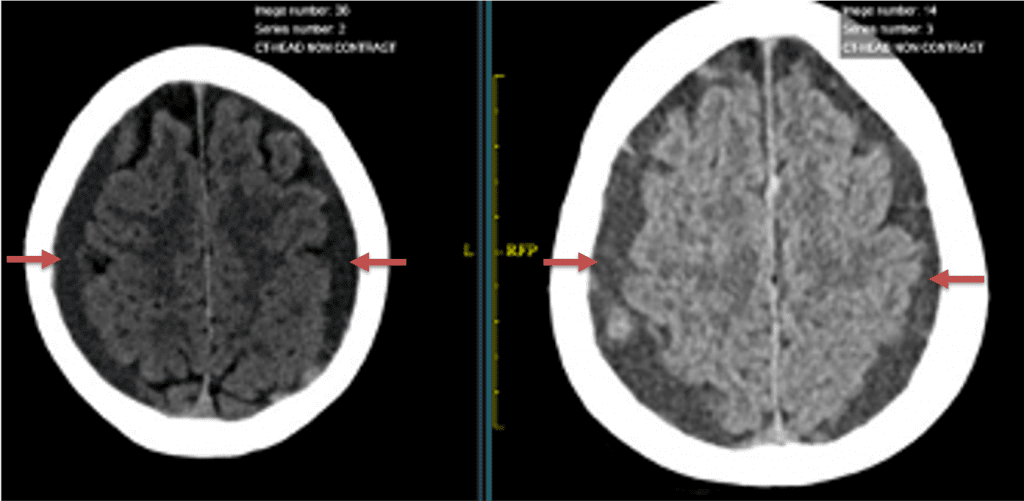

A woman in her 80s developed mild dizziness and headache following incidental trauma working in her garage one day. She presented several weeks later to the ER and was diagnosed with bilateral subdural hematomas, which were initially managed with observation, low dose Decadron, considering the mildness of symptoms, advanced age, and history of CLL with thrombocyptopenia (<100k). Over the next 4 weeks, the collections remained relatively stable with evidence of slight growth (10 to 12 mm thickness, and 2 mm right to left shift) on NCT (Figure 1. A and B).

Figure 1. A) 6 weeks post mild trauma B) 4 weeks post mild trauma demonstrates stable subacute subdural collections with mild growth and sulcal effacement.